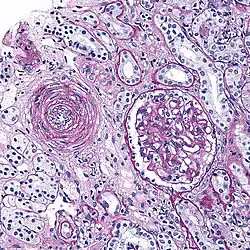

Micrograph showing hyaline arteriolosclerosis in the kidney. PAS stain.

Also arterial hyalinosis and arteriolar hyalinosis refers to thickening of the walls of arterioles by the deposits that appear as homogeneous pink hyaline material in routine staining.[3] It is a type of arteriolosclerosis, which refers to thickening of the arteriolar wall and is part of the aging process.[4]

It is often seen in the context of kidney pathology.[4][8][9] In hypertension only the afferent arteriole is affected, while in diabetes mellitus, both the afferent and efferent arteriole are affected.[8][9] It is also seen in retina and brain,[10] where retinal infarcts and small brain infarcts, or lacunes can occur.

Hyaline arteriolosclerosis is a major morphologic characteristic of benign nephrosclerosis, in which the arteriolar narrowing causes diffuse impairment of renal blood supply, with loss of nephrons.[5] The narrowing of the lumen can decrease renal blood flow and hence glomerular filtration rate leading to increased renin secretion and a perpetuating cycle with increasing blood pressure and decreasing kidney function.[12]